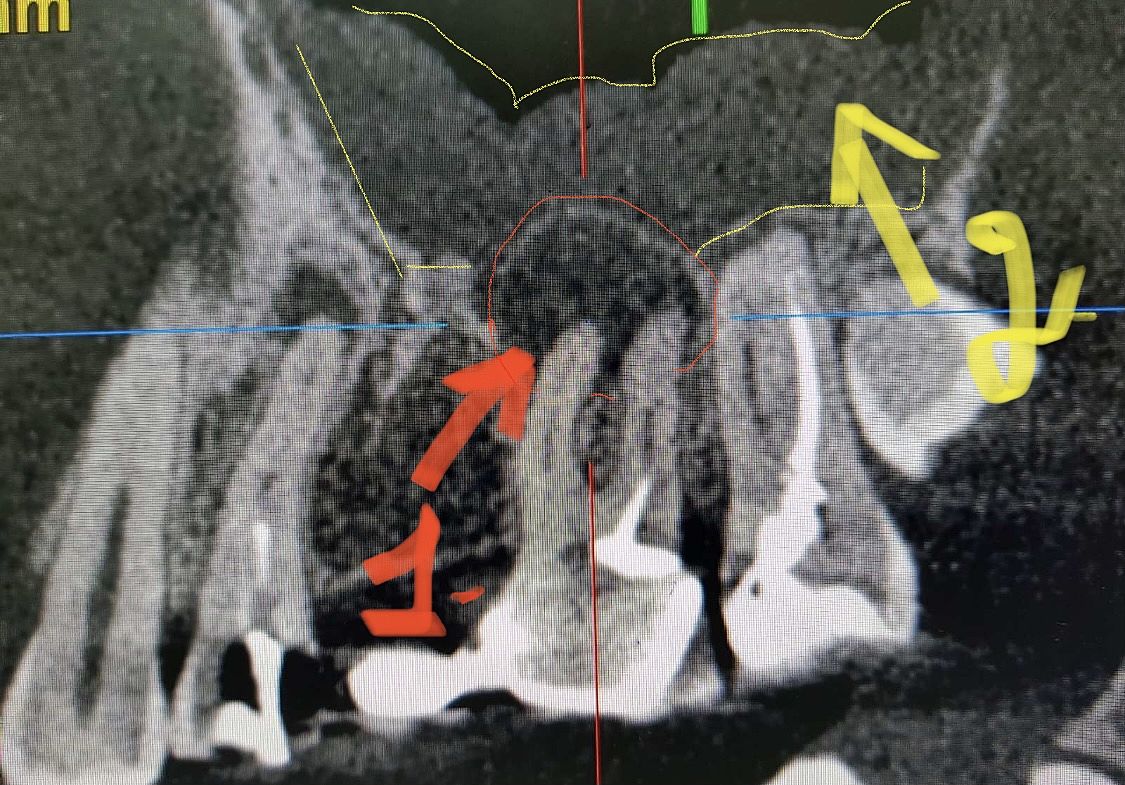

Добрый день, если проблема только в некачественном эндодонтическом лечении, либо в том, что в зубе «умер» нерв, то хороший эндодонтист решит Вашу проблему. Скидываю снимок пациента , чтобы было понятней. На фото до лечения видно, что каналы незапломбированны должным образом. Первая стрелочка-«киста». Вторая- отёк (воспаление) слизистой в гайморовой пазухе , как результат. На втором и третьем фото видно, что каналы запломбированы и всё зажило)). Так что ищите хорошего врача и всё будет ок).